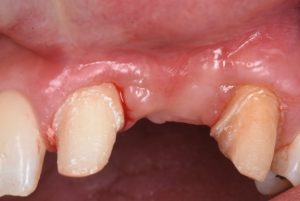

This video presents Part 2 of a staged pontic site development protocol, performed five months after the initial soft tissue augmentation. The objective of this second surgery is to further enhance soft tissue volume and achieve root coverage in preparation for a future fixed partial denture (FPD).

The procedure demonstrates the use of a horizontal vestibular incision with tunneling to mobilize the soft tissues and elevate the papillae. An autogenous connective tissue graft (CTG) harvested from the palate and maxillary tuberosity is utilized to augment tissue thickness. Additionally, a xenogenic bone graft is placed over the crestal area to serve as a space-maintaining scaffold and support vertical tissue stability.